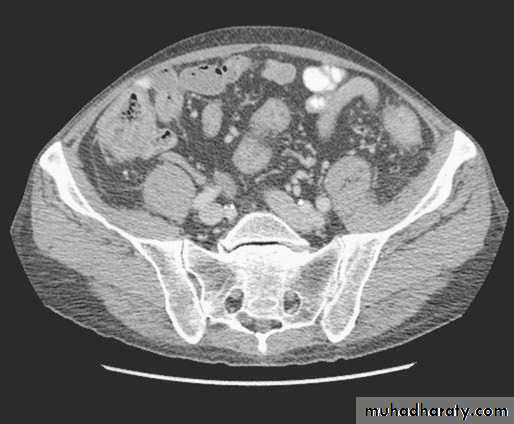

CT findings in pancolitis

Significant thickening of the colonic wallInflammatory stranding in the colonic mesentery